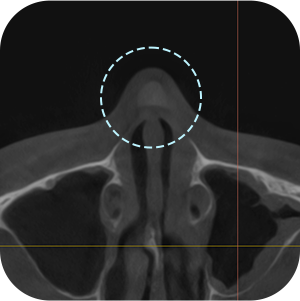

以前、手術の 保形物情報確認

鼻中隔湾曲症など 機能的問題確認

現在の保形物の 位置確認

鼻のCT撮影、どうしても必要ですか?

A再手術ですので、もっと精密に診断する必要があります。

内部の機能的な問題を正確に診断することで

安全な手術が可能となります。

鼻再手術は徹底した分析が重要です。

3D-CTを通じて正確な分析が

できるから! - 03